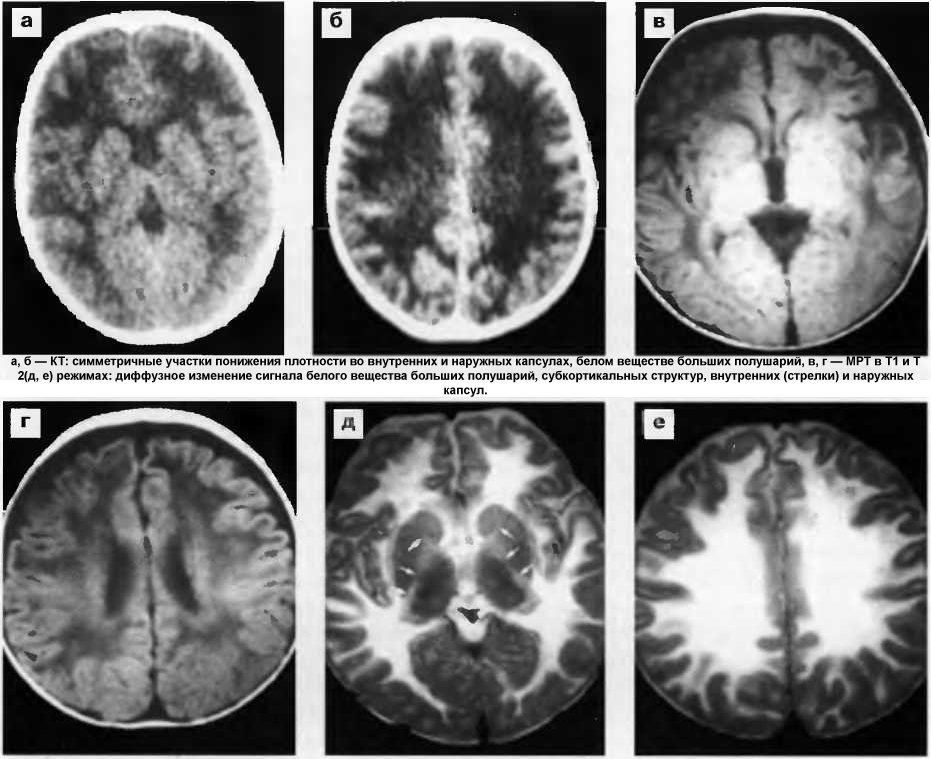

Атеросклеротическая энцефалопатия головного мозга — хроническая прогрессирующая патология, развивающаяся на фоне атеросклероза и гипертонии. На поздних стадиях характеризуется деменцией, протекает с острой очаговой симптоматикой или прогрессирующими неврологическими нарушениями, связанными с разрушением белого вещества. В некоторых случаях под термином болезнь Бинсвангера понимают подострое поражение головного мозга с быстро развивающимся слабоумием на фоне злокачественного течения гипертензии. Заболевание диагностируется достаточно часто.